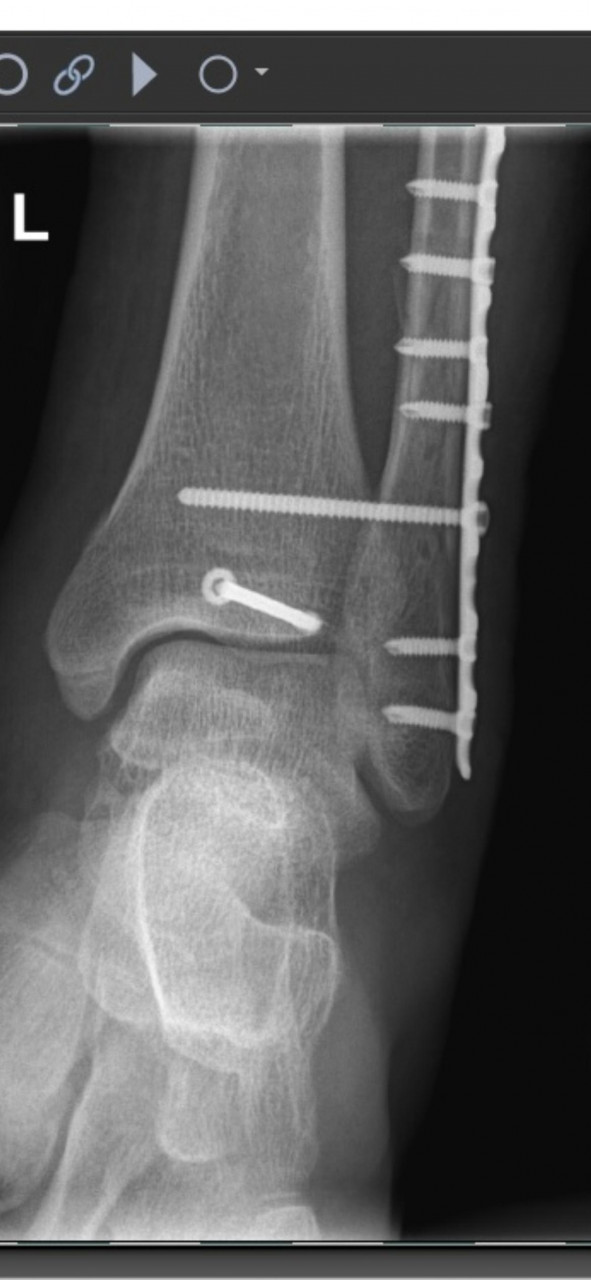

Сегодня, спустя 7 недель, сделал контрольный снимок голеностопа. Прикладываю снимки после оперрации и спустя семь недель. Хочу узнать ваше мнение. Можно начинать лфк, начинать приступать на ногу?

1. После операции https://iimg.su/i/aR7iEg

2. После операции https://iimg.su/i/8z8B6b

Здравствуйте. По контрольному снимку через 7 недель конструкция стабильна, видно начало консолидации. Можно постепенно начинать щадящую ЛФК (пассивные и активные движения, изометрические упражнения) и опираться на ногу частично в ортезе, полную нагрузку можно после 10-12 недель и повторного контроля. Каждый случай индивидуален, и без очного осмотра точную рекомендацию дать сложно. Поэтому обратитесь к своему ортопеду, для точной оценки.